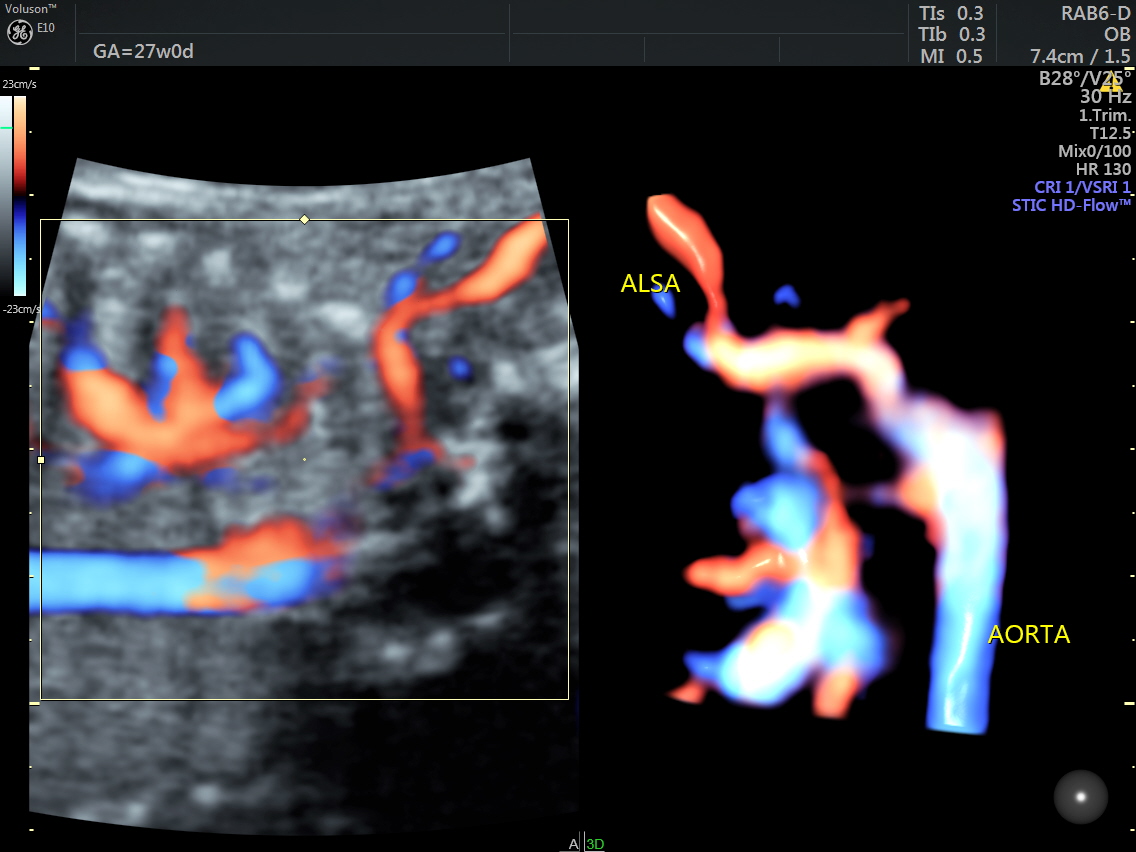

IMG_20160520_2_9 Published June 17, 2016 at 1136 × 852 in Rt aortic arch and aberrant left subclavian artery ← Previous Next →